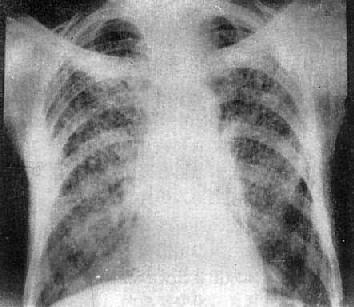

粟粒型肺结核病灶小,透视常难以辩认,故拟诊急性粟型肺结核时应摄片检查。病变早期整个肺野可呈毛玻璃样密度增高。约10日后可出现均匀分布的1.5~2mm大小、密度相同的粟粒状病灶,正常肺纹理常不能显示(图3-1-22)。经过适当治疗后。病灶可在数月内逐渐吸收,偶尔以纤维硬结或钙化而愈合。病变恶化时,可以发生病灶融合,表现为病灶增大,边缘模糊,甚至形成小片状或大片状影,并可干酪样化而形成空洞。

图3-1-22 急性粟粒型肺结核

两肺野布满粟粒状病灶,分布均匀,肺门大

(2)亚急性或慢性血行播散型肺结核:系少量结核杆菌在较长时间内多次进入血流播散至肺部所致。患者抵抗力较强,症灶多以增殖为主,临床症状可不明显或有反复的发热、畏寒或轻度结核中毒症状如低热、盗汗、无力、消瘦等。